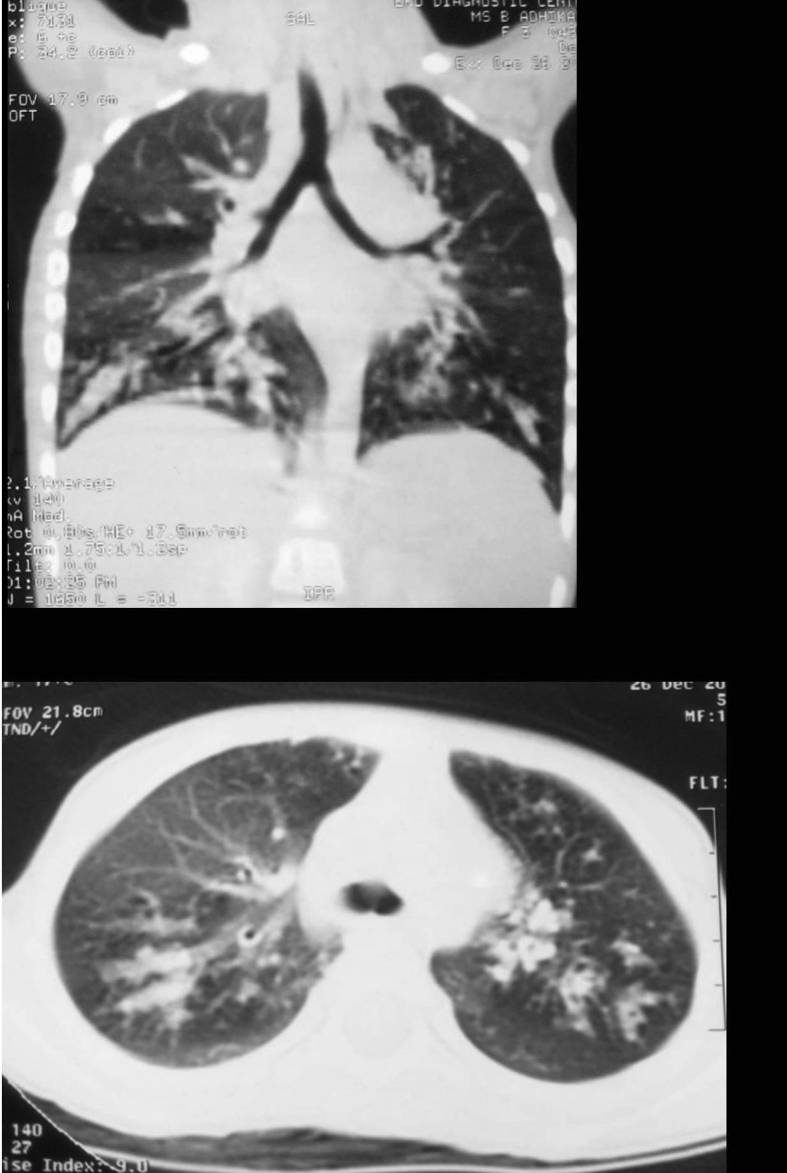

Investigations revealed a total leukocyte count of 13,500/mm3 with 6% eosinophil (absolute eosinophil count of 800/mm3). Serum IgE level was elevated at 2500ng/ml. Tests were negative for tuberculosis. Sweat chloride estimation and CFTR gene mutation was negative thereby ruling out cystic fibrosis. HRCT chest showed changes suggestive of bronchiectasis, ‘signet ring sign’ (Fig. 5). Skin prick tests were positive for Aspergillus fumigatus and Aspergillus versicolor. Serum IgE antibodies specific against Aspergillus fumigatus was found to be positive. As like the other patient, the patients responded favourably to treatment (oral corticosteroids alone of total 2 months duration).

Fig. 5.

HRCT chest showing ‘signet ring sign’.